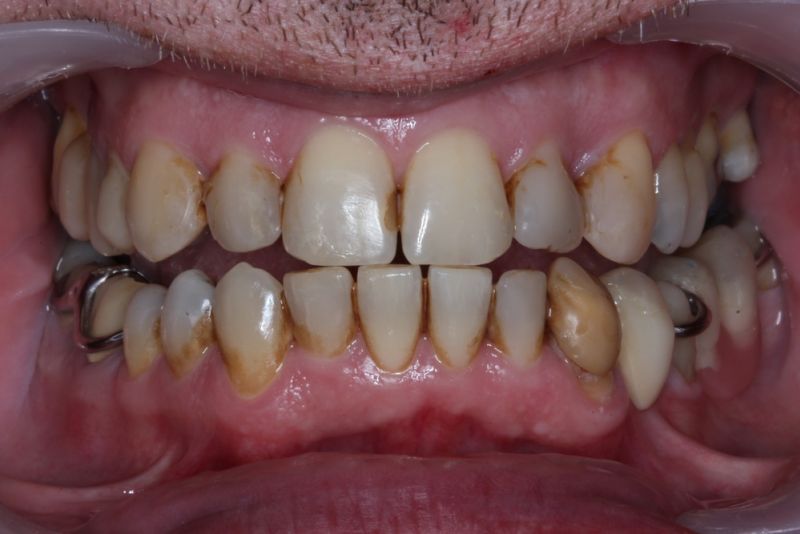

Erkennbar ist die massive Abweichung der habituellen Bisslage von der neuromuskulär zentrierten Bisslage.